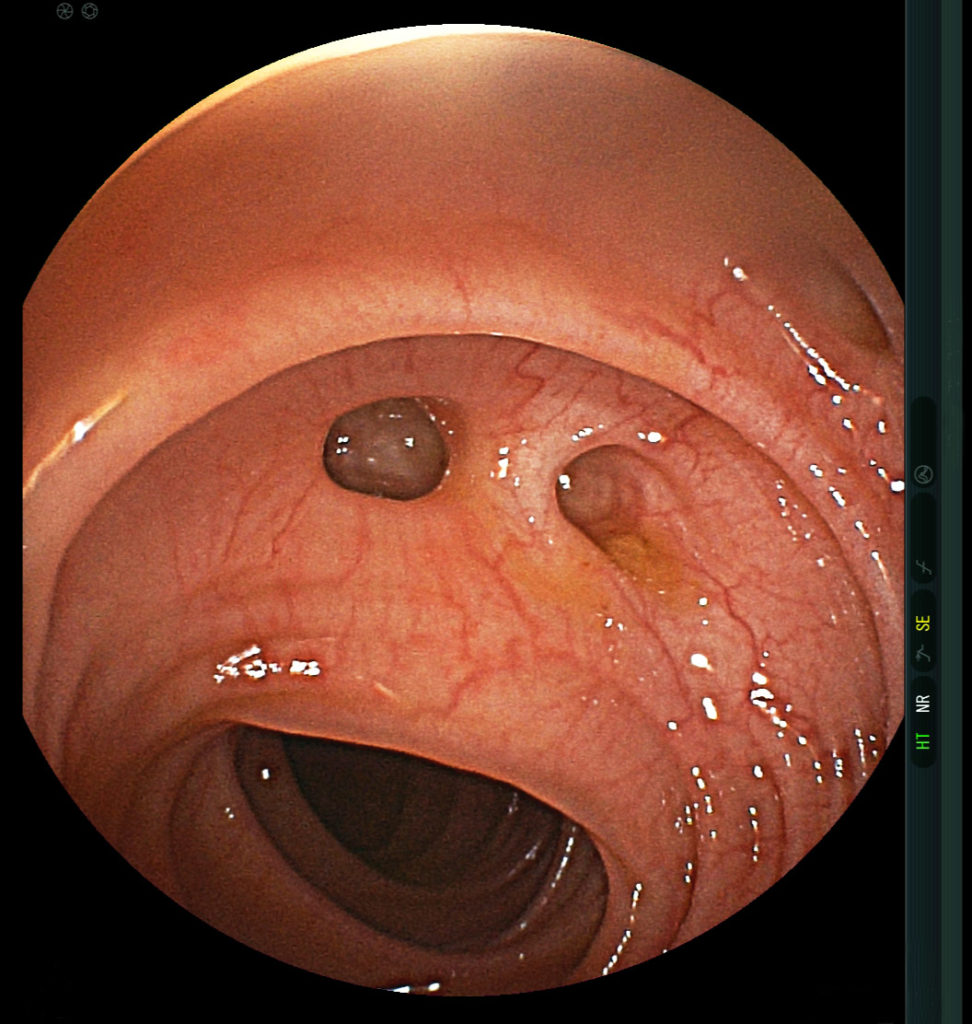

대장 게실 자체를 확인하는 가장 좋은 방법은 바로 대장 내시경입니다. 대장 내시경을 통해 실제로 게실을 눈으로 확인하는 것이 가장 좋습니다. 단, 어떤 게실은 대장 내시경으로도 잘 볼 수 없는 경우도 있습니다.

대장 내시경으로 본 게실(가운데 2개) (출처 : 위키피디아)

또한 게실염이 심한 경우, 대장 내시경의 접근이 어려운 경우에는 복부 전산화단층촬영(복부 CT)을 먼저 시행하고 이후에 가능할 때 대장 내시경을 시행합니다.